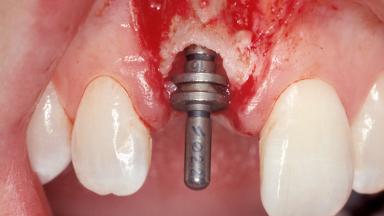

A 30-year-old female patient was referred to the office for the treatment of tooth 11. Her chief concern at the initial visit was to inquire, “Why is my tooth pink?” Upon clinical examination, it was determined that tooth 11 had a previous history of trauma and that the clinical crown had become noticeably pink in color as a result of internal resorption. This diagnosis was confirmed radiographically, indicating a large radiolucency involving the central and distal portions of the clinical crown. It was determined that restoration of this tooth was not possible, and that extraction was indicated. The presence of a mid-line diastema, which the patient wanted to reproduce, directed the treatment plan for tooth replacement utilizing a dental implant.

Type of Implants One-Piece|Reduced-Diameter

Placement Protocol Immediate implant placement

Tooth Site Maxillary incisor or canine

Socket Morphology Single-root socket

Socket Integrity Sufficient, with intact bone walls

Bone Volume Sufficient, with intact walls